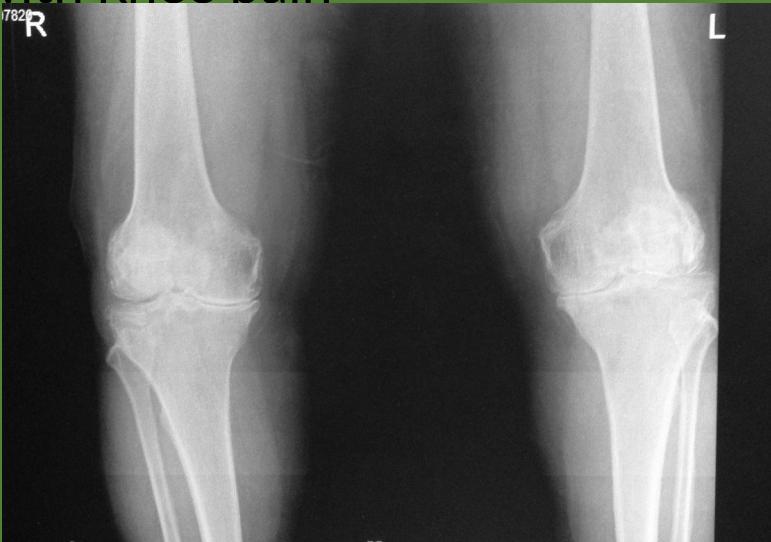

Case 1: Lady with Chronic Knee Pain

- 54 year old lady, presented to the clinic with pain in both knees for 3 years

Imaging Studies

- Standard Radiographs:

- Both knees AP standing views (weight-bearing)

- Lateral views of both knees

- Skyline view (patellofemoral assessment)